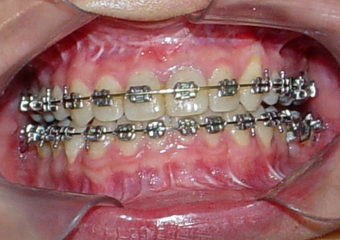

Mordida inicial